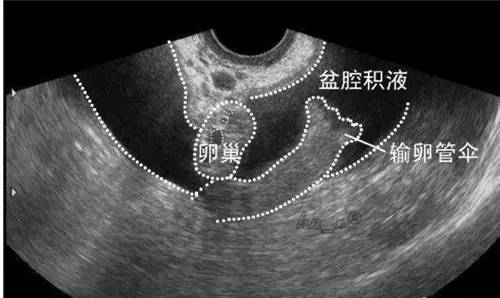

2、盆腔积液

如果体检报告上写有盆腔积液,不要惊慌哦,盆腔积液和盆腔炎并不是一种疾病。盆腔积液大多数是生理现象,没有不舒服就不需要治疗。

正常情况下盆腔内会产生一些渗出液,但量比较少,主要作用是润滑脏器表面、减少脏器之间的摩擦,而且具有一定的防御功能。在排卵期卵泡破裂后的卵泡液回流到盆腔内,月经期间少量经血流入腹腔,均可出现少量的盆腔积液,但这些都是正常的生理现象,可以自行吸收,不需要进行治疗。

病理性盆腔积液多发生在盆腔炎性疾病之后,比如子宫内膜炎、盆腔腹膜炎、输卵管炎等等,就需要根据病因进行治疗,还要说一句,盆腔积液不一定是盆腔炎,但盆腔炎是可以诱发盆腔积液的。